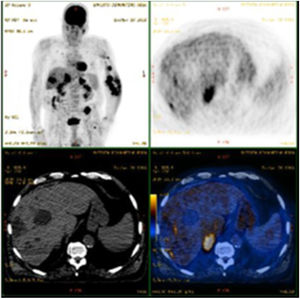

Partial and/or complete response was achieved in the majority (65.8%) of cases. A third developed – mainly mild (venous stasis and/or lymphedema) – complications. However, transformation to an anaplastic variant arose in one case (Fig. 2) and another patient was subsequently diagnosed with non-Hodgkin lymphoma. Although overall mortality was 36.8%, mortality directly related to KS was only 8% (n = 3). Two patients had classic KS: one died aged 83 following transformation to anaplastic KS despite four cycles of bleomycin; the other died due to visceral progression of the disease (gastrointestinal and pulmonary involvement already present at the moment of diagnosis, later progressing with liver metastases – Fig. 3). The third patient was heart transplanted, dying with gastrointestinal and pulmonary metastases of KS, even after immunosuppression adjustment and 6 cycles of vinorelbine.

PET-CT scan showing the progression of Kaposi’s Sarcoma with metastatic involvement of the liver in a patient with previously known gastrointestinal and pulmonary involvement. This patient later died despite multiple treatments, including doxorubicin, alfa-interferon, paclitaxel, vinorelbine, and radiotherapy.